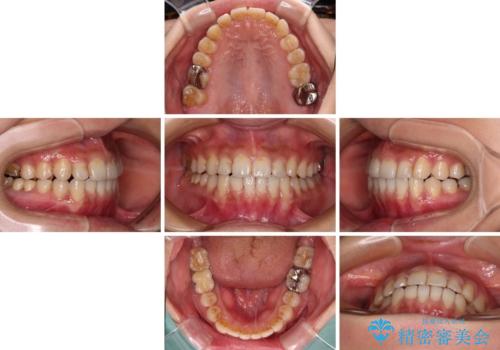

- 上下のクロスバイトと前歯のデコボコを気にして来院された患者様です。

骨格的に下顎がやや前方にあり、奥歯にクラウンが装着されているため、矯正治療後半の不安定な咬み合わせを避けるのであればワイヤー矯正がおすすめとなりますが、希望によりインビザラインにて治療を行うこととしました。

インビザラインを用い、IPR(歯と歯の間を削る)と歯列全体を拡大させることで、歯並びを整えていくこととしました。

懸念されたとおり、右下のクラウン部分が全く咬み合わず、仕上げの段階で治療期間が長くなりました。